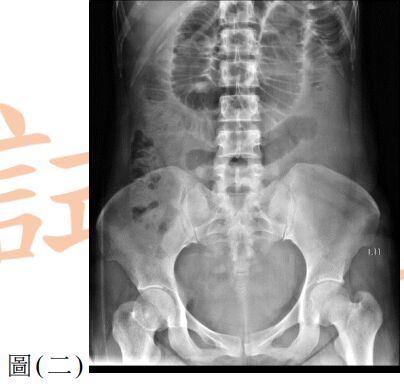

12. 一位 25歲男性因呼吸困難至急診就醫,主訴2天前工作撞擊到右側胸部,胸部X光檢查如圖(三),下列處置何者較適當?

(A) 立即給予右側胸管置入引流 (B) 觀察呼吸困難狀況並給予肌肉鬆弛劑 (C) 立即安排胸腔鏡手術治療 (D) 安排胸部電腦斷層檢查確立診斷